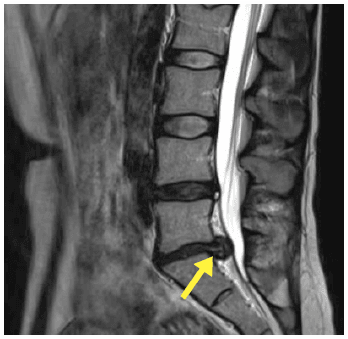

This image is an MRI of a patient’s lumbar spine (lower back), showing a significant disc bulge. You can see the disc slipping out of place and squashing the spinal cord (white bit) – can’t you? This must be painful, right? And surely it could slip further and cause...